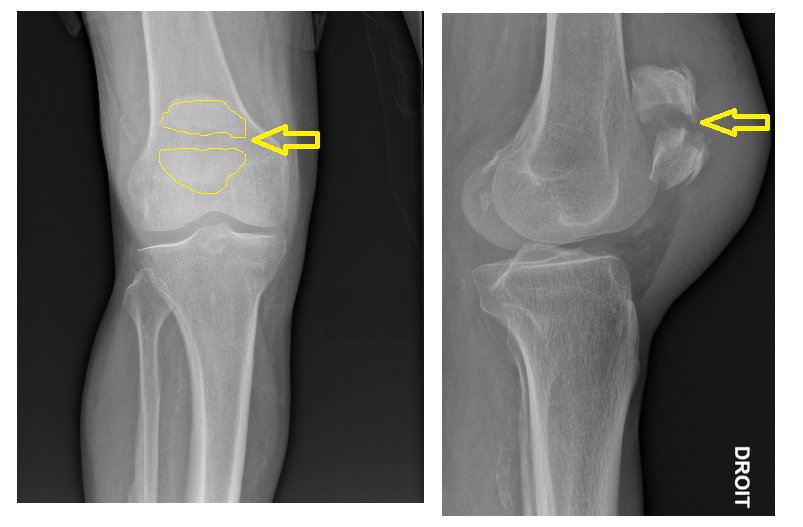

From slidetodoc.com

Fractures de la rotule Traits de fractures Les Fracture De La Rotule ce document présente les types, les indications, les précautions, les risques et le déroulement du traitement des fractures. la fracture du genou résulte le plus souvent d’un accident de sport ou d’une chute. une fracture du genou peut toucher le plateau tibial ou la rotule, et provoquer une douleur intense et une impossibilité de marche. tout. Fracture De La Rotule.

Fractures de la rotule Traits de fractures Les Fracture De La Rotule Découvrez les causes, les symptômes et les traitements possibles de cette pathologie orthopédique aiguë. ce document présente les types, les indications, les précautions, les risques et le déroulement du traitement des fractures. tout savoir sur la fracture de la rotule, un os qui protège l'articulation du genou : la fracture de la rotule est une blessure grave. Fracture De La Rotule.